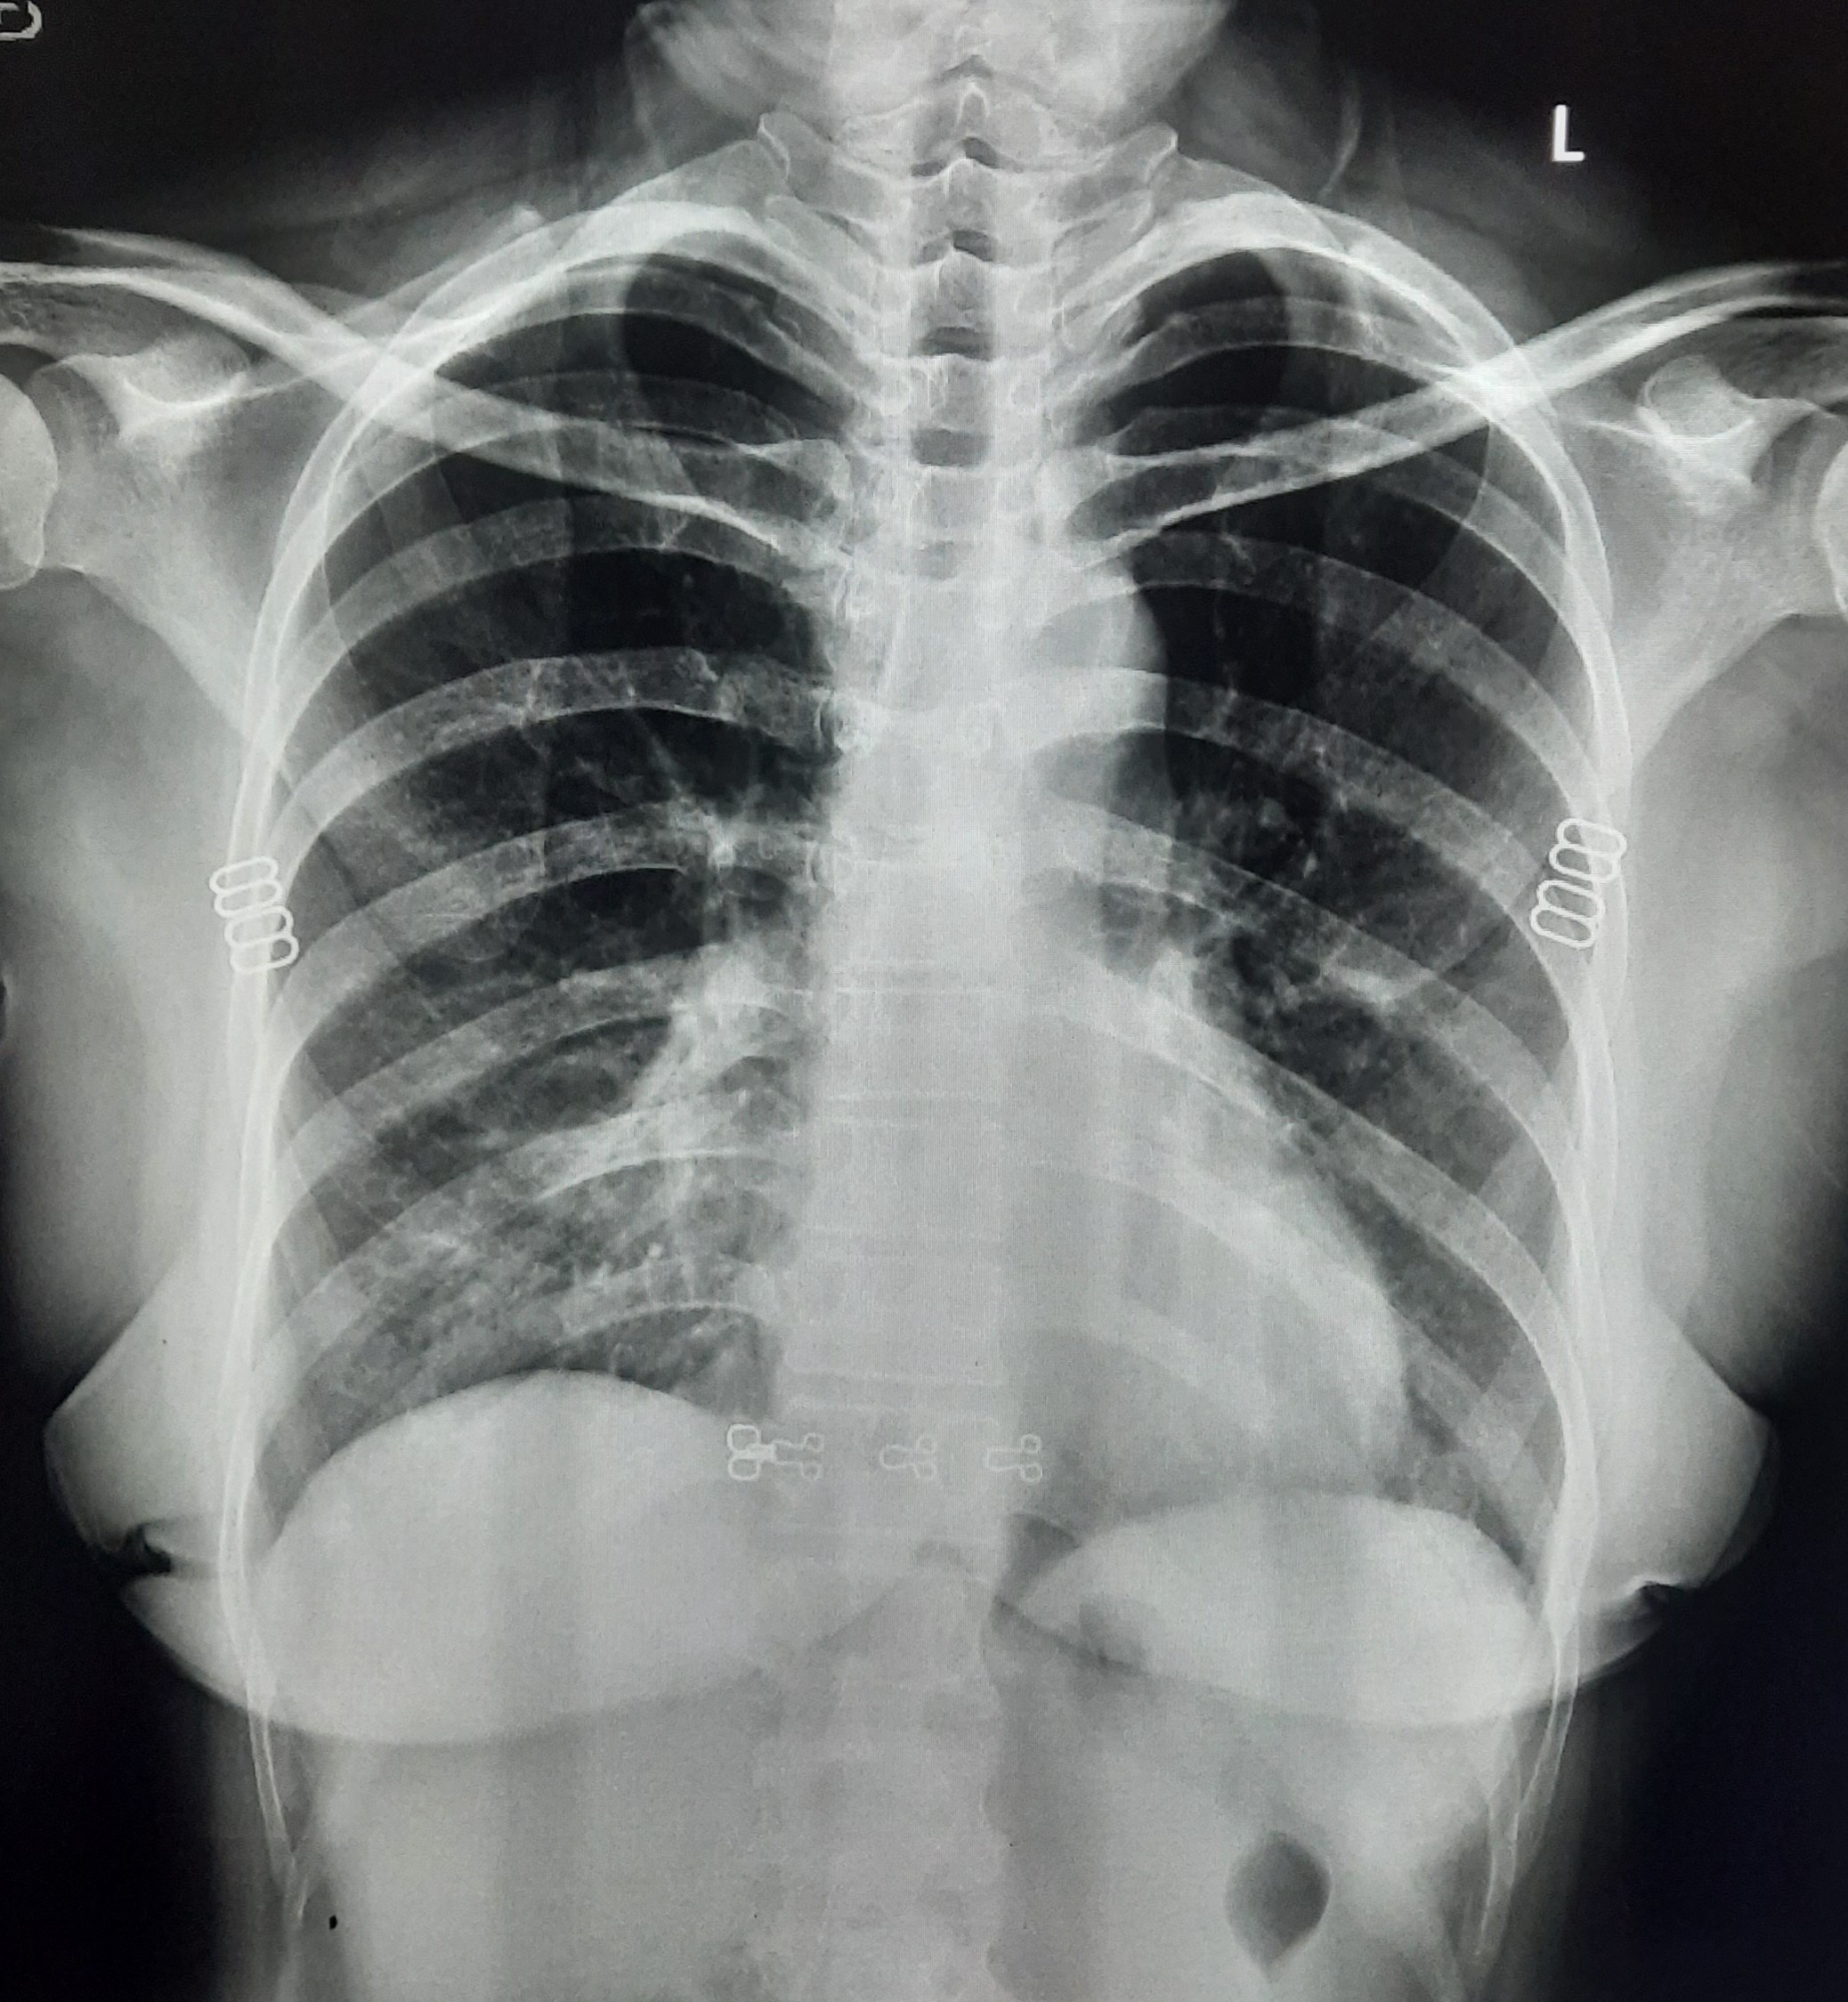

| 152 | IGGMC, Nagpur, Nagpur | P2 | 29-4320 | Dewakabai Thakare | Consent taken on Paper | 80 Yrs. |

Provisional Diag : Post TB Sequel

Final Diag : Post TB sequelae with emphysematous Hyperlucency |

Post TB Sequelae | Left Lower Zone Ill Defined Opacities Present With Hyperlucency Left Lower Zone | Abnormality visible on x-ray |